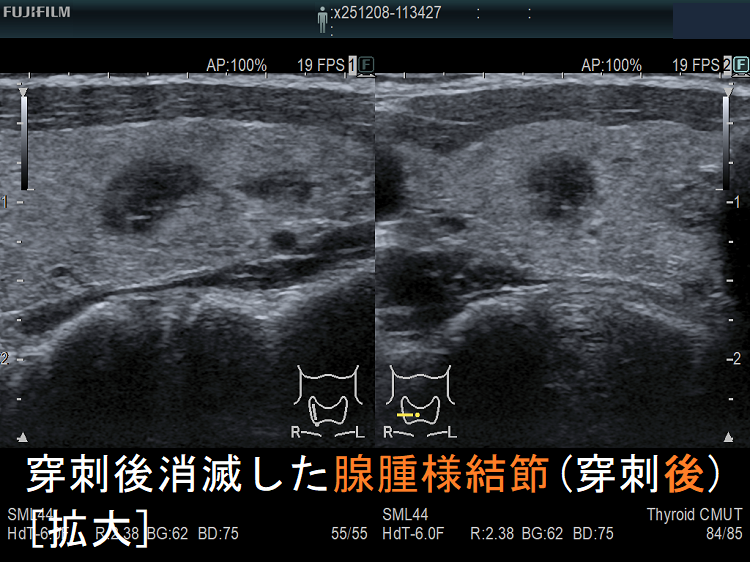

![穿刺後消滅した腺腫様結節(穿刺後) [拡大] 穿刺後消滅した腺腫様結節(穿刺後) [拡大]](../images/basic/basic5/images20251216212323.png)

![穿刺後消滅した腺腫様結節(穿刺後)ドプラーモード[拡大] 穿刺後消滅した腺腫様結節(穿刺後)ドプラーモード[拡大]](../images/basic/basic5/images20251216212330.png)